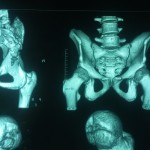

Image Challenge 13, Paediatric #Hip

Popular Answer may not imply right answer, Follow our twitter handle for the right answer, Click for Answer